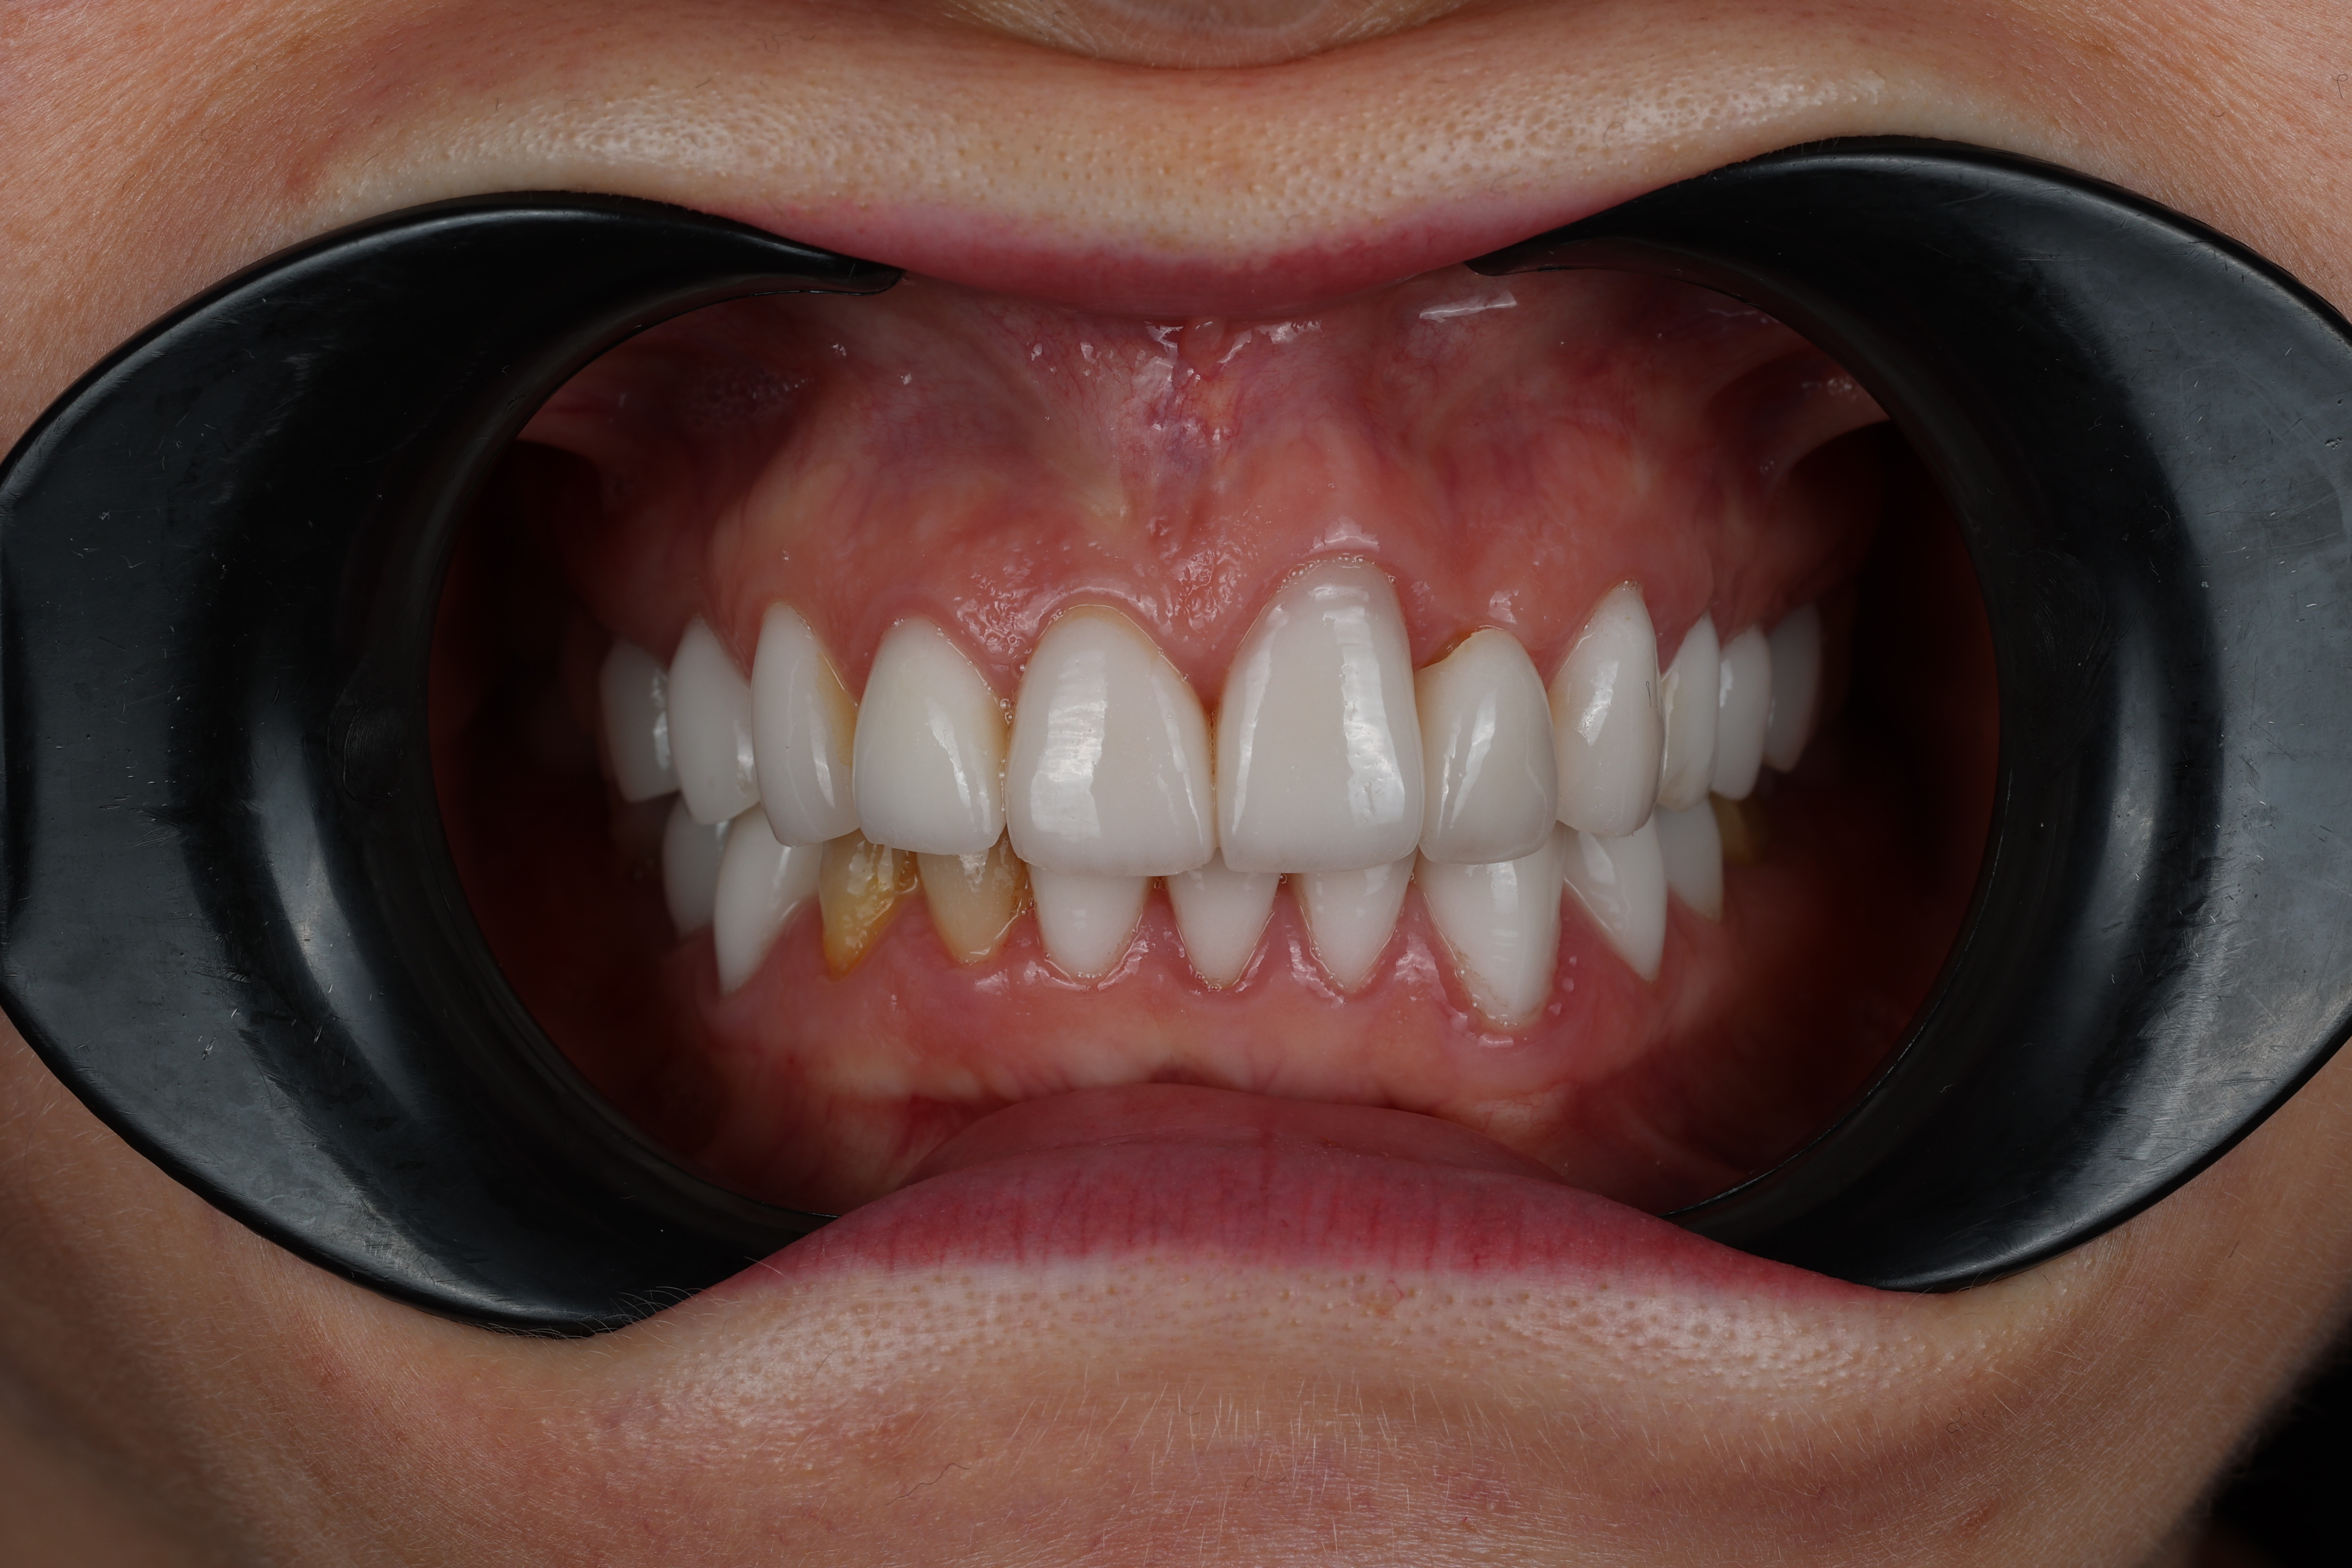

📷 We completed a photo protocol, designed a physiological bite, and gave her temporaries to adapt with. Then we created custom Emax veneers and crowns, perfectly tailored to her function and aesthetics.

3️⃣ After — When You Feel Like Smiling Again

✨ Today, Oksana is transformed — radiant, relaxed, and fearless.